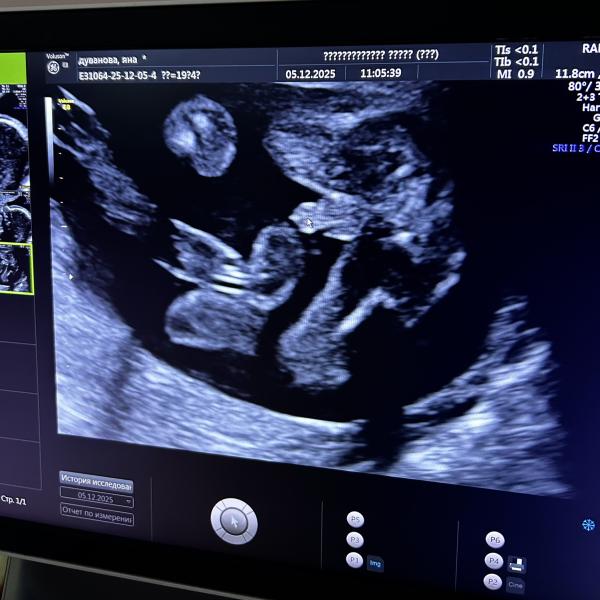

Когда на втором скрининге не успела задать вопрос о том, не отвалилась ли пиписька, как человек быстренько сунул её на весь экран.

Спасибо - пожалуйста😂

Это волшебное чувство, видеть этого человека на экране, и понимать что совсем скоро он будет на моих руках🙏🏼